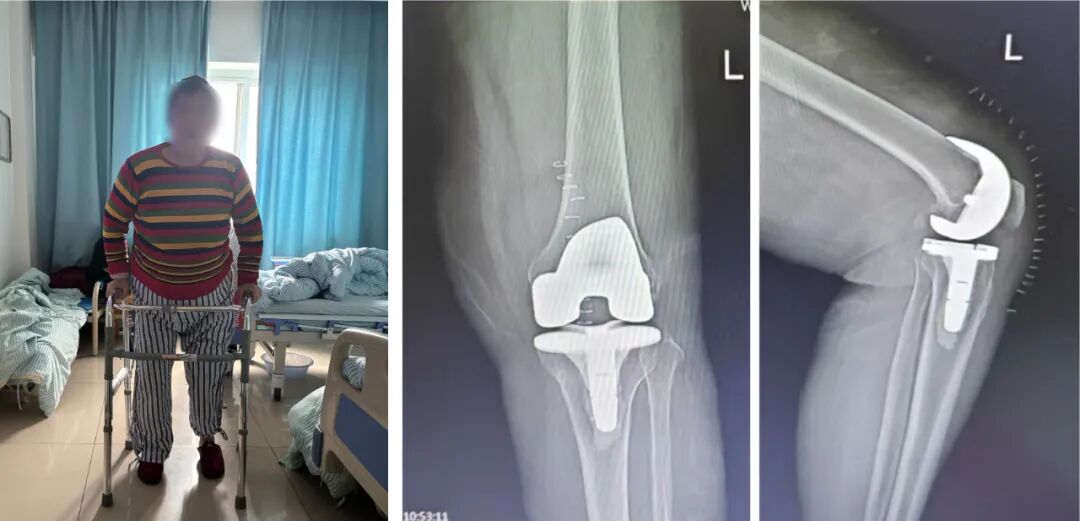

为尽快解决患者的问题,骨科团队制定了详细缜密的手术方案,入院第三天,在麻醉科、手术室等相关临床医技科室的密切配合下,为赵阿姨进行了“左侧全膝关节置换术”。术后恢复良好。

“连续疼痛十多年的腿可算不再折磨人了,恢复得还可以,最近我自己天天都在病区里锻炼了……”昨日在病房里见到赵阿姨时,她激动的表示,马上就要出院了,术后当天就下地了,第4天就能行走自如了,心情也好了很多,相信再过不久便能重新享受上悠闲的散步时光。